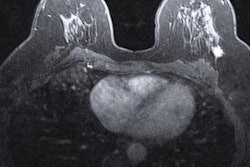

Researchers at the National Institutes of Health (NIH) have found that high levels of particulate air pollution are tied to increased breast cancer incidence.